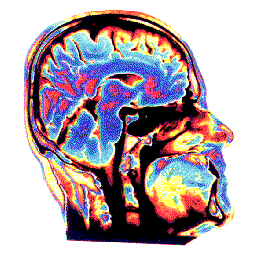

Température tete portable Alan Baddeley et Hitch (1974) ont modifié ce modèle en introduisant la mémoire de travail ( infos).